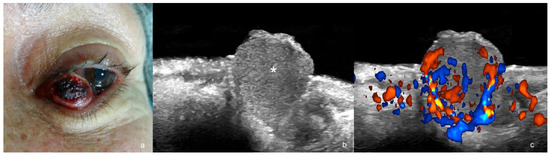

4. Merkel Cell Tumor

| Merkel Cell Tumor | hypoechoic, nodule, pseudonodule, exophytic, ill-defined borders | high degree |